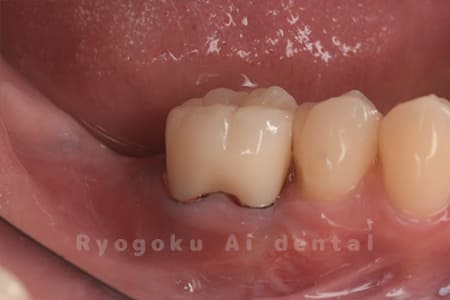

Case14

-

- 抜歯原因

- 重度カリエス

- 治療内容

- クラウンレングスニング治療

- 治療費用

- 44,000円

他院で抜歯と言われた、とのことでご来院された患者さまです。クラウンレングスニングを行い、保存致しました。大変満足して頂けました。

<リスク・副作用>

治療後、痛みや違和感、出血、腫れなどが出る事があります。喫煙者、糖尿病などの方の場合、歯が生着しない場合があります。